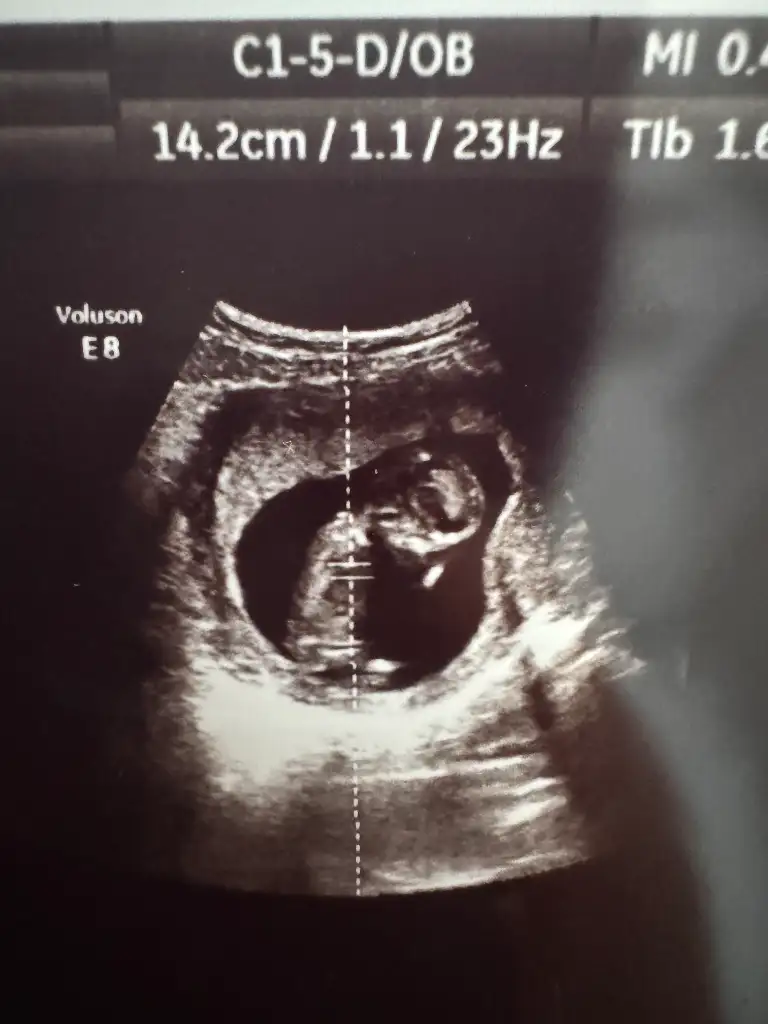

Ve son olarak size güzel bir ultrason görüntüsü bırakmak isterdim ama inanın çamaşır makinesiyle çekilse daha güzel çıkardı bebeğim.

Cinsiyet tahmini bile yapılmaz baksanıza 🫢

Bence gitmelisin canım. Attığın görselde bebek bile zor seçilirken ayrıntılara nasıl bakabiliyor ki bu kadar pixel olan bir ultrasonla